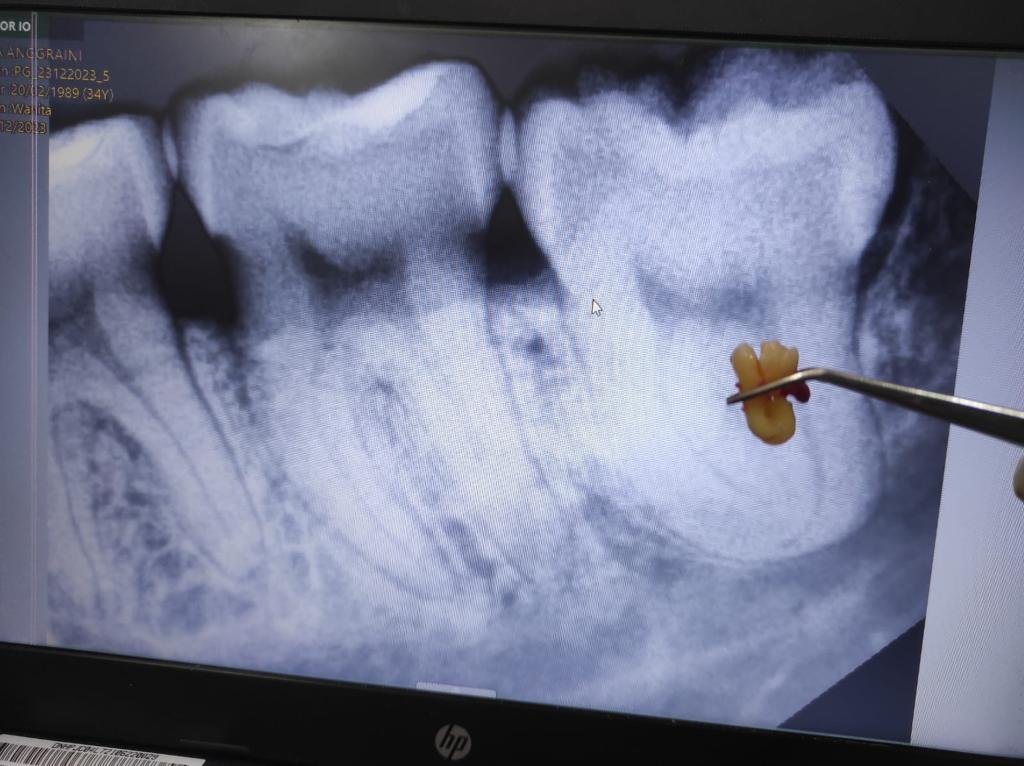

4. Pengangkatan gigi

Bila gigi sulit dicabut, dokter membaginya menjadi beberapa bagian lalu mengangkat potongan satu per satu.

Rata-rata operasi odontektomi membutuhkan waktu 30–60 menit, tergantung tingkat kesulitan gigi.